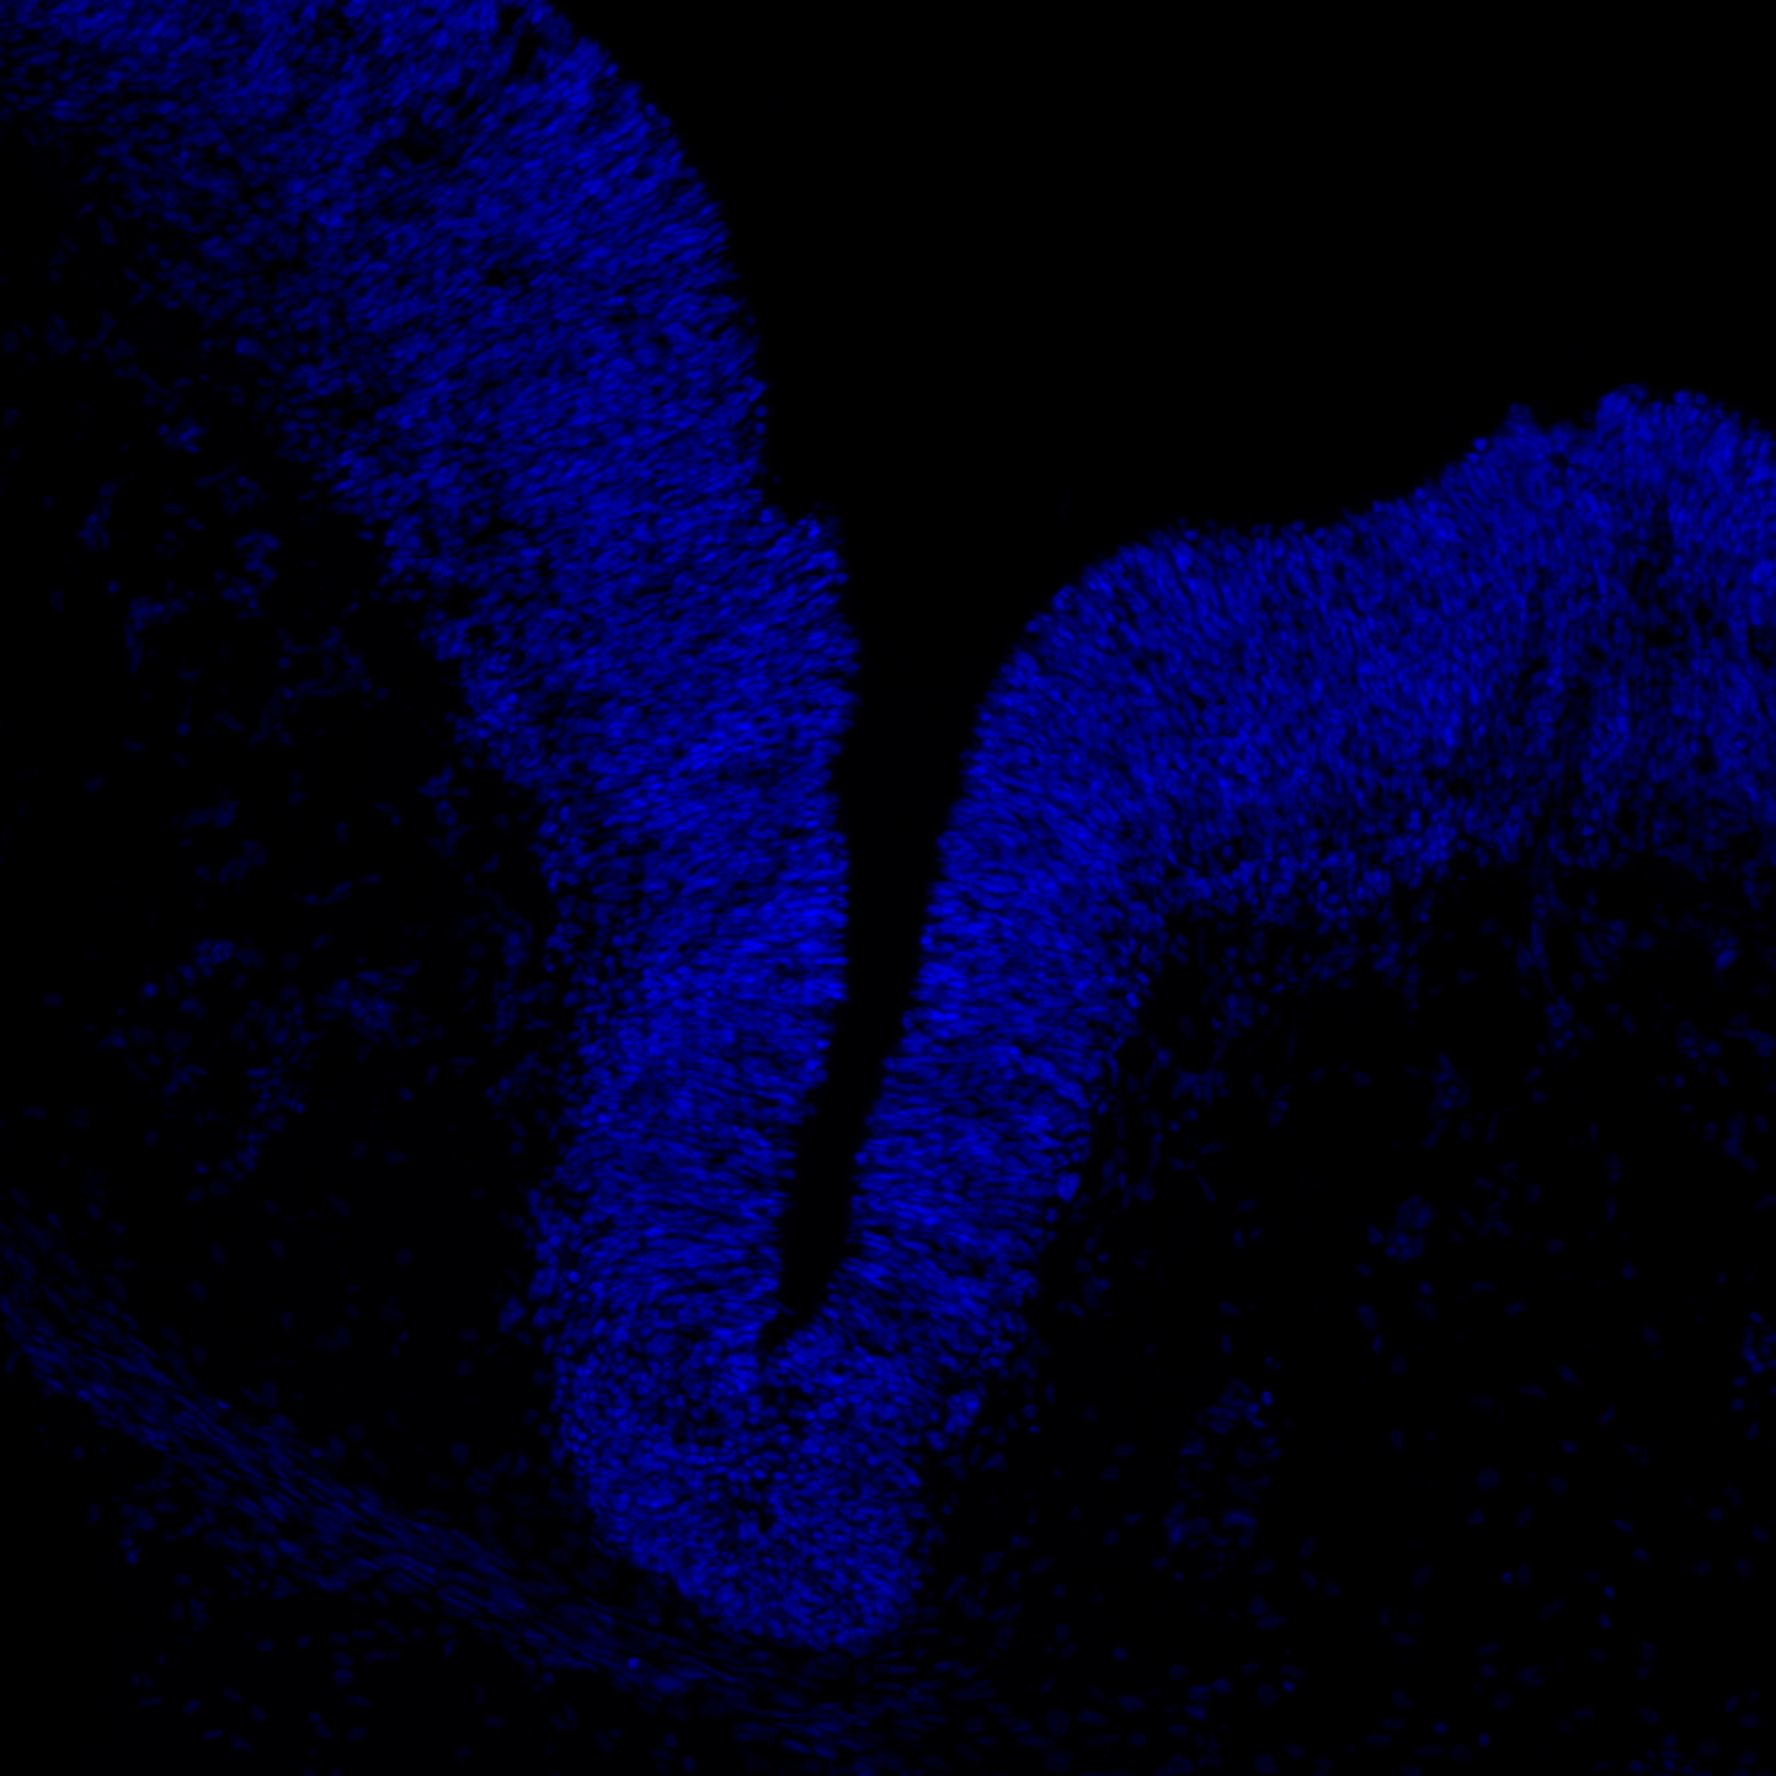

7PCW

DAPI

7PCW human midbrain